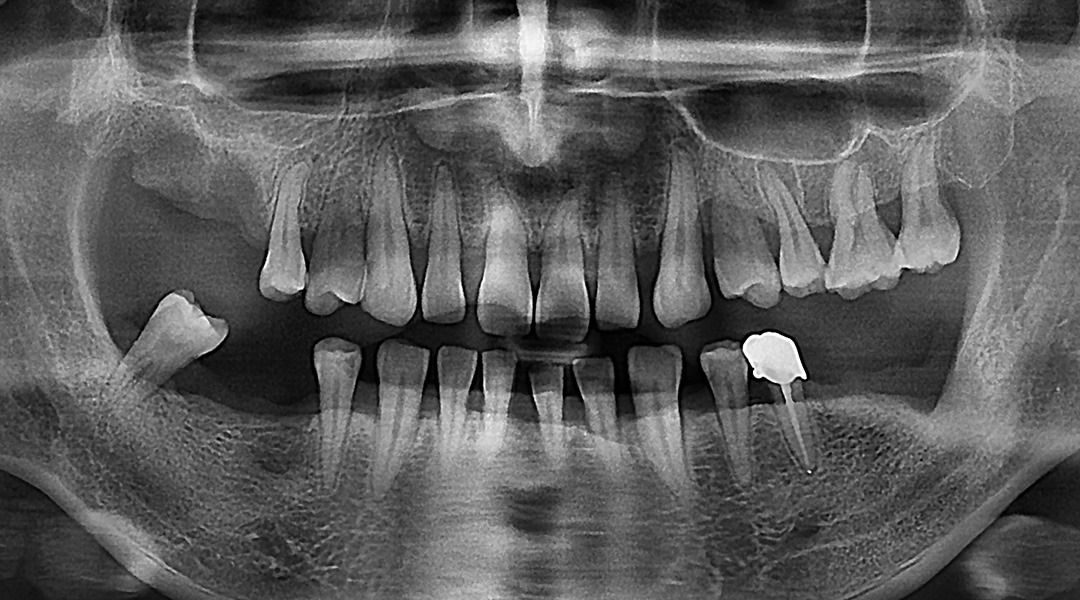

BEFORE & AFTER

갤러리치과의원의 전후 사진을 확인해보세요.

- 충치 / 일반치료

- 무통임플란트